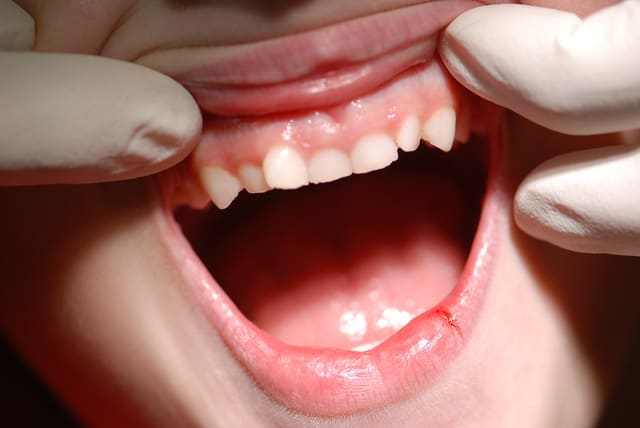

Patient 9 ans

La mère vient consulter car les Inc. centrales sont absentes

bien qu’on lui ait extrait les lactéales, il y a 2 ans

@+ Bjc.